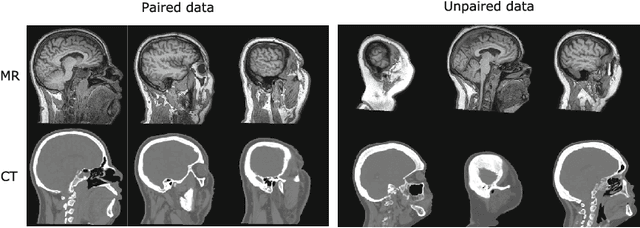

Abstract:MR-only radiotherapy treatment planning requires accurate MR-to-CT synthesis. Current deep learning methods for MR-to-CT synthesis depend on pairwise aligned MR and CT training images of the same patient. However, misalignment between paired images could lead to errors in synthesized CT images. To overcome this, we propose to train a generative adversarial network (GAN) with unpaired MR and CT images. A GAN consisting of two synthesis convolutional neural networks (CNNs) and two discriminator CNNs was trained with cycle consistency to transform 2D brain MR image slices into 2D brain CT image slices and vice versa. Brain MR and CT images of 24 patients were analyzed. A quantitative evaluation showed that the model was able to synthesize CT images that closely approximate reference CT images, and was able to outperform a GAN model trained with paired MR and CT images.